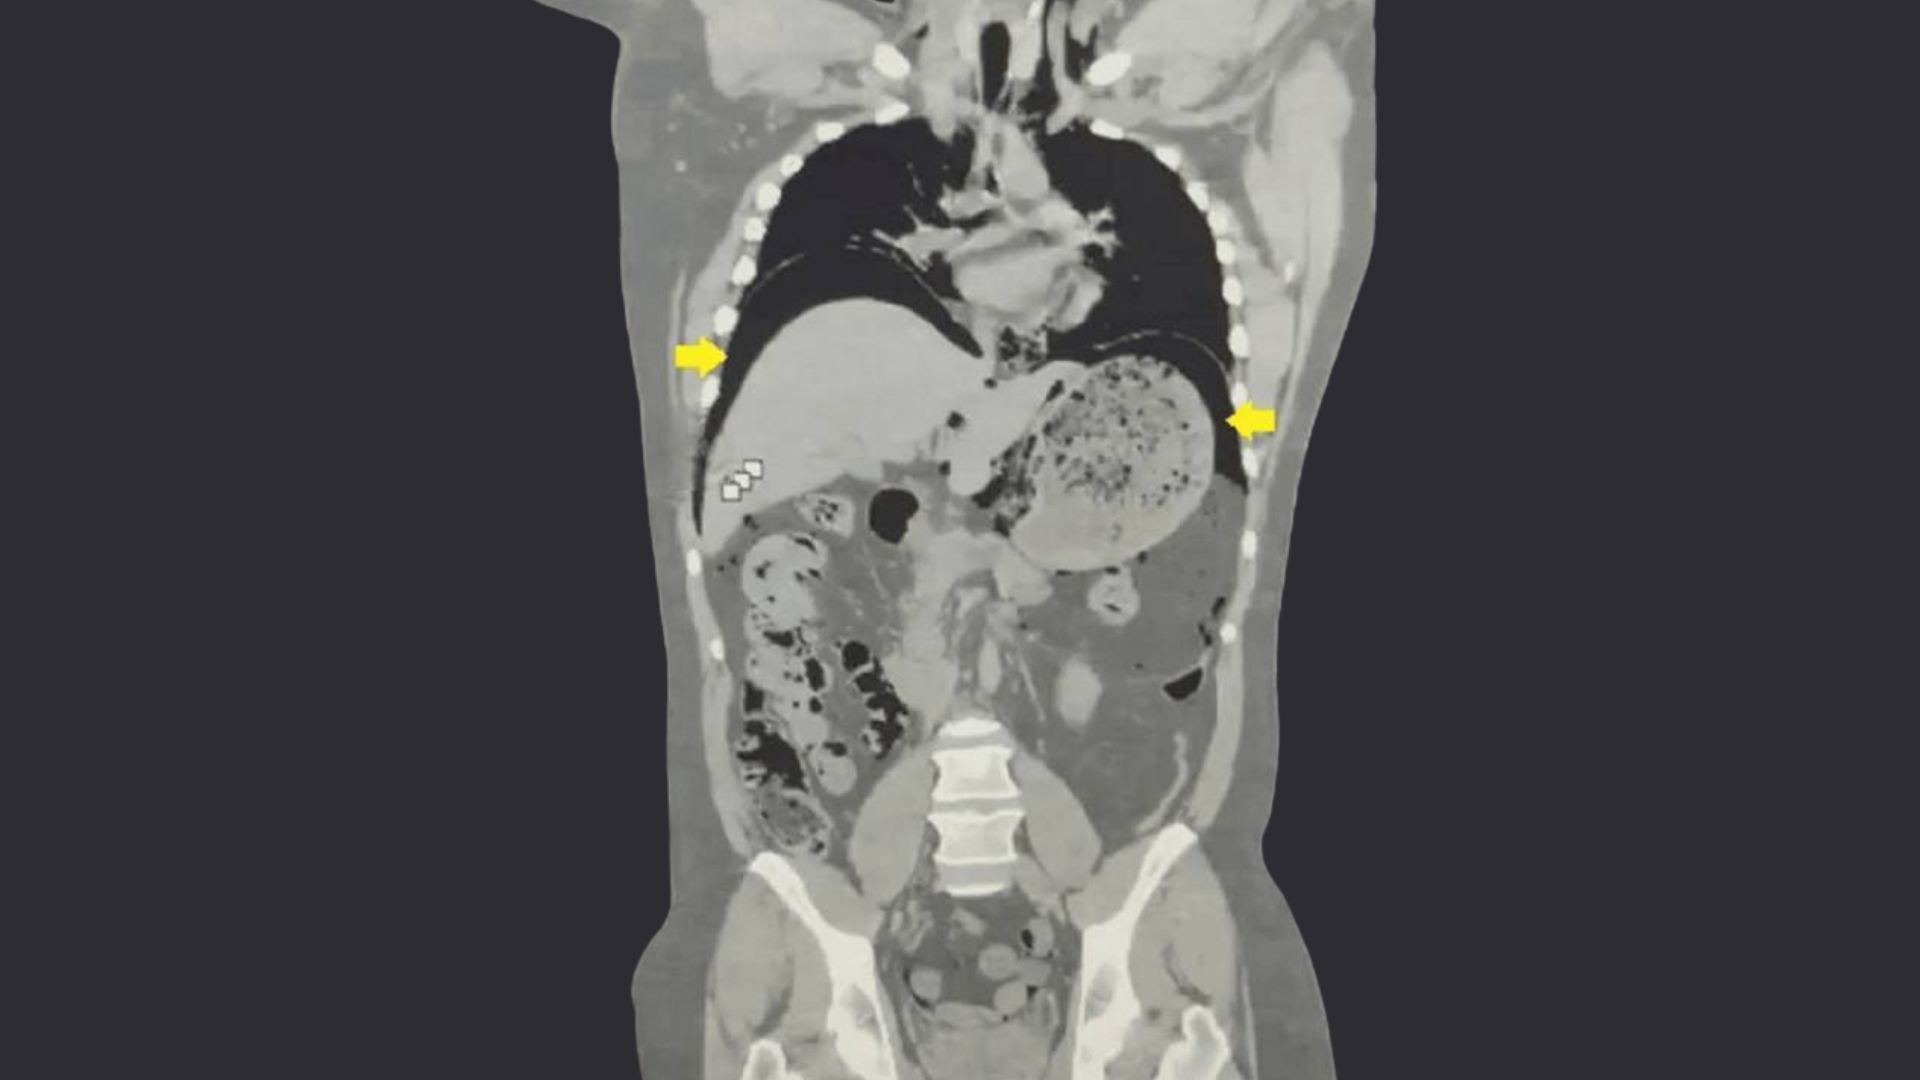

A CT scan confirmed their worst suspicion. Trapped nitrogen gas had collected in a layer just above the man’s stomach and below his lungs, a condition doctors call pneumoperitoneum. The liquid nitrogen, still in its fluid state when consumed, had rapidly converted to gas inside his warm stomach. The expansion was so forceful that it tore a hole in the stomach wall. His organ had, in effect, been inflated like a balloon until it burst, releasing gas into spaces where no gas should exist.